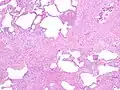

Histology

The histologic hallmarks of UIP, as seen in lung tissue under a microscope by a pathologist, are interstitial fibrosis in a "patchwork pattern", honeycomb change and fibroblast foci (see images below).[6] [7]

Appearance of honeycomb change in a surgical lung biopsy at low magnification. The dilated spaces seen here are filled with mucin. Hematoxylin-eosin stain, low magnification.